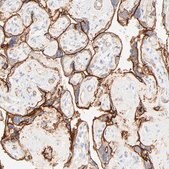

Anti-ITGA5 antibody produced in rabbit, a Prestige Antibody, is developed and validated by the Human Protein Atlas (HPA) project . Each antibody is tested by immunohistochemistry against hundreds of normal and disease tissues. These images can be viewed on the Human Protein Atlas (HPA) site by clicking on the Image Gallery link. The antibodies are also tested using immunofluorescence and western blotting. To view these protocols and other useful information about Prestige Antibodies and the HPA, visit sigma.com/prestige.

• IHC tissue array of 44 normal human tissues and 20 of the most common cancer type tissues.